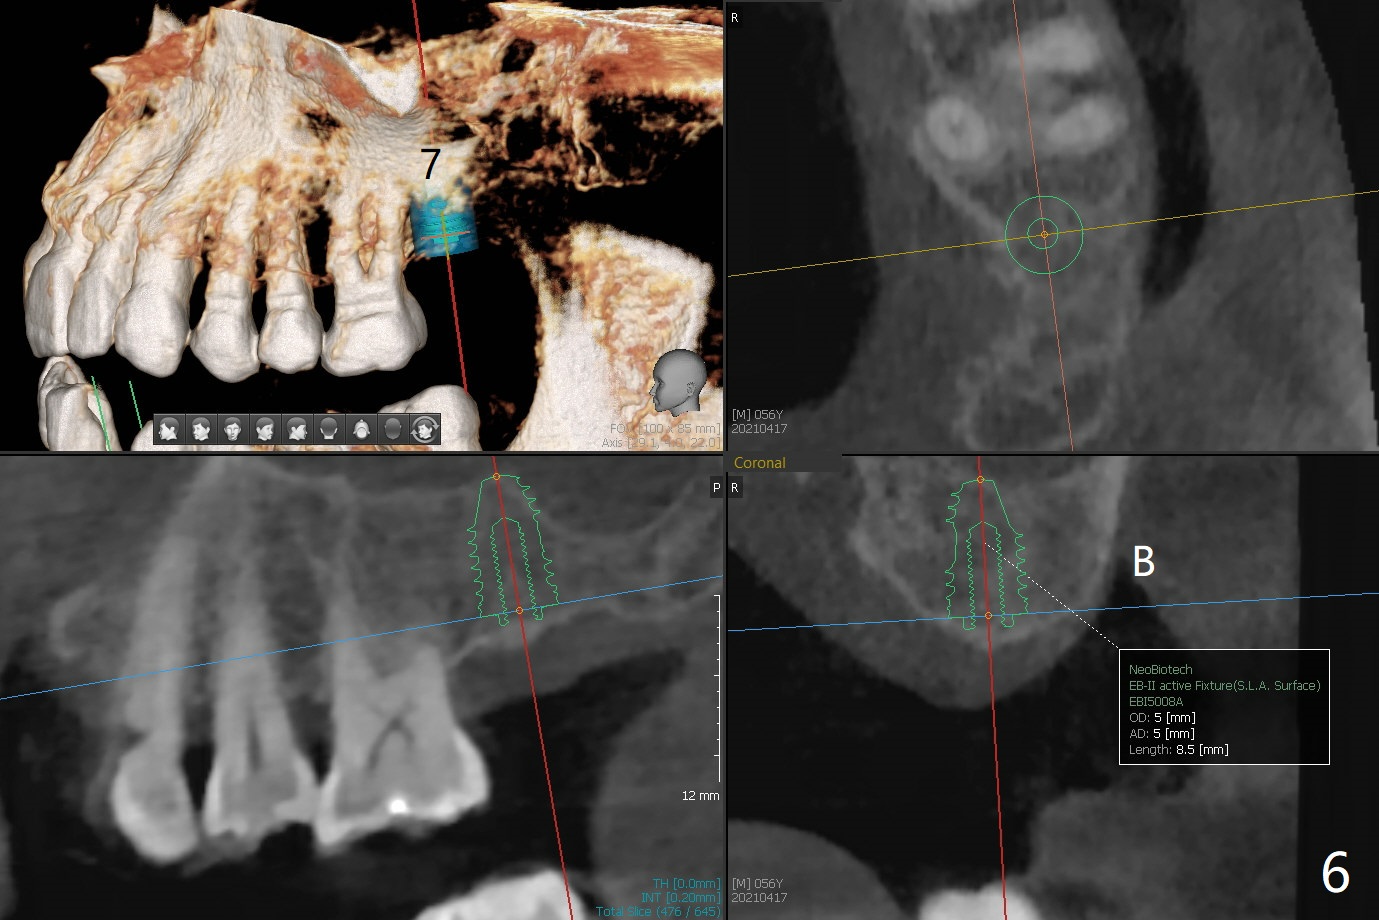

56岁男右下7位点保存一个月,还缺失4个牙齿(图一),左下2,3牙槽嵴特别狭窄,骨皮质为主(图二),应该植入2.0,2.5毫米植体(图三,四),避免复杂植骨术。而右上3骨质也狭窄,但是骨质密度低,几乎松质骨(图五),如果采纳骨膨胀术(高速倒转),植体可以大于4.0毫米,防止植体断裂。左上7骨质宽,但是短,5x8.5毫米植体可能胜任功能(图六)。如果植入10毫米植体,需要做上颌窦提升。